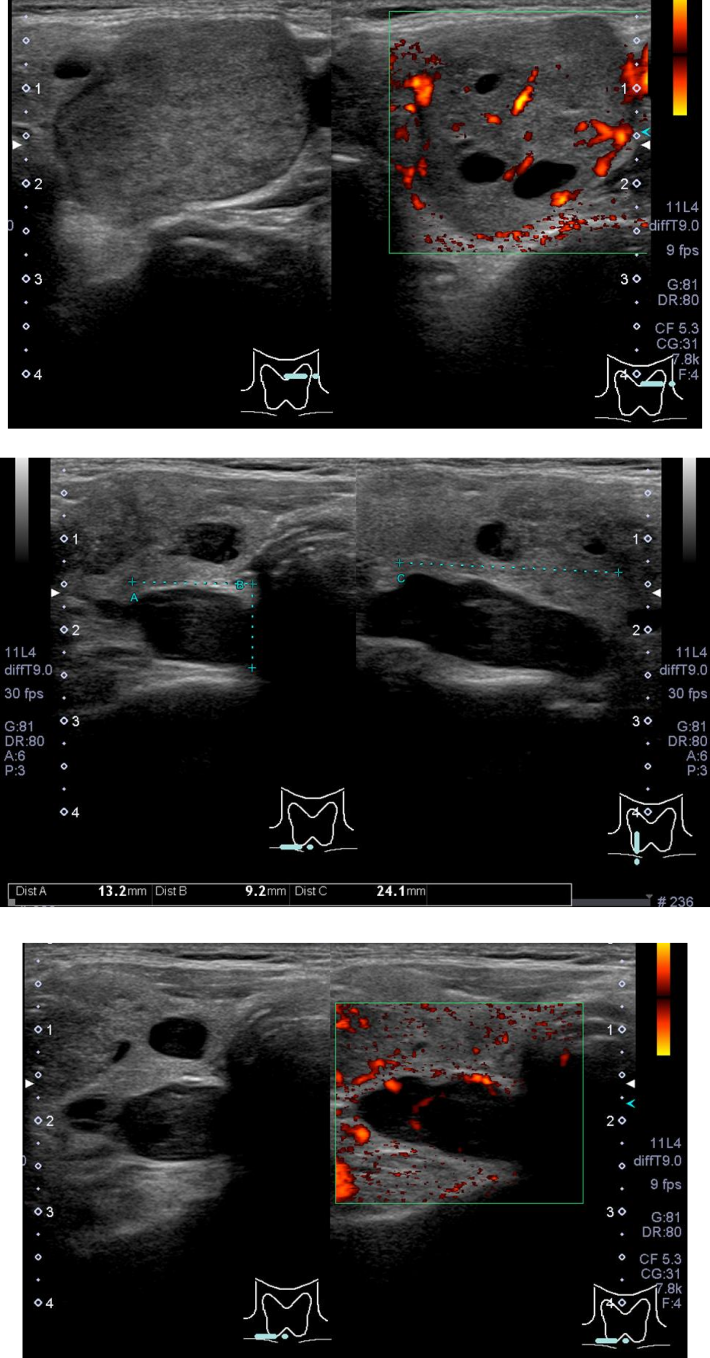

@Ebσ‘BƒGƒR[

EϊŽh‹zˆψΧ–Ef

@EΆγ‹ΙŽξᇁF–c‘εΧ–E‘BŽξ‹^‚’